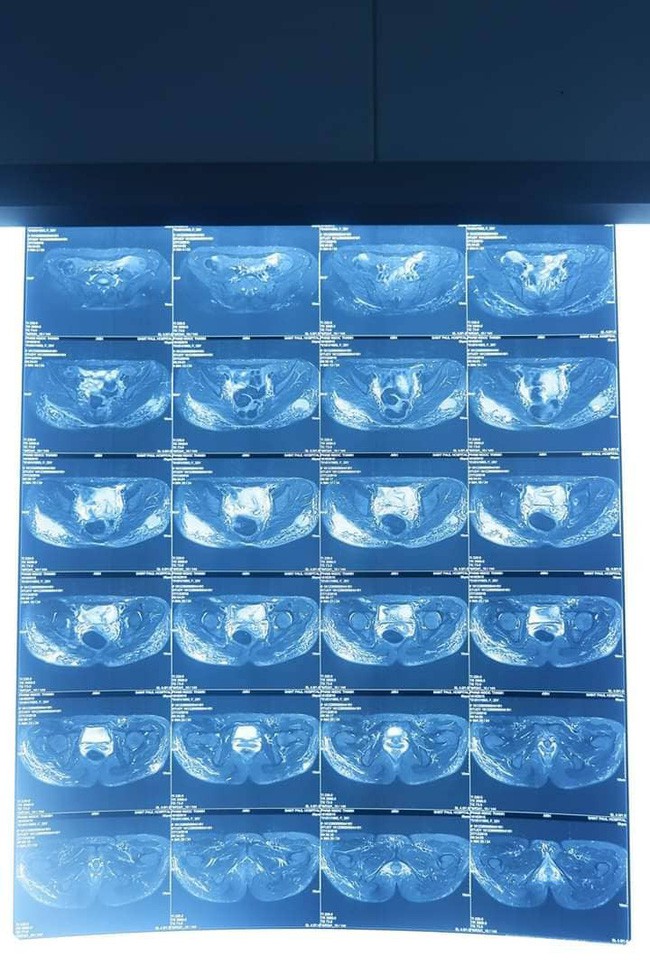

ThS.BS Nguyễn Đình Minh – Trưởng khoa Phẫu thuật tạo hình thẩm mỹ và hàm mặt cho biết: Bệnh nhân nhập viện trong tình trạng có 2 khối áp xe đang nhiễm trùng, sưng, tấy đỏ ở mông. Qua kết quả khám, chụp cộng hưởng từ, các bác sĩ thấy 2 khối dịch lớn có tính chất trong suốt, kèm theo rất nhiều hạt nhỏ rải rác khắp 2 bên mông bệnh nhân. Hình ảnh điển hình dựng lại trên cộng hưởng từ là hình ảnh các hạt silicon trắng xoá như mưa sao băng.

Qua kết quả khám, chụp cộng hưởng từ, các bác sĩ thấy 2 khối dịch lớn có tính chất trong suốt, kèm theo rất nhiều hạt nhỏ rải rác khắp 2 bên mông bệnh nhân.